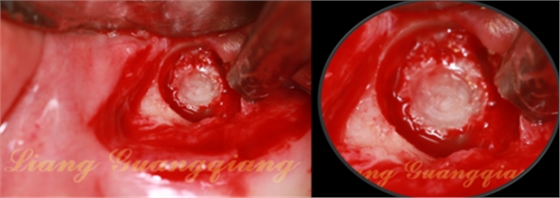

膜收腰的狹窄區(qū)剛好卡在洞口,大部分的膜被平攤在上頜竇膜下方:1,防止殘余的囊液污染骨粉。2.防止大顆粒的骨粉刺傷上頜竇膜。下方植入骨粉。

骨粉要塞實,外面的生物膜正好折下來蓋住窗口

總有老師問我:開孔鉆轉(zhuǎn)速多少?落空感表示頰側(cè)骨壁瞬間穿通,會不會把膜刺破?轉(zhuǎn)速800——200轉(zhuǎn)之間,充分注水。有停止環(huán)保護(hù)不會插入太多。最主要的是大家有沒有觀察到窗口內(nèi)上頜竇膜中央部位的圓形小骨片?開孔鉆獨特的設(shè)計,所有病例鉆頭頰側(cè)骨壁后,上頜竇膜與鉆頭之間一定會有一個小骨片保護(hù)上頜竇膜,所以轉(zhuǎn)速大小都不會造成膜穿孔。